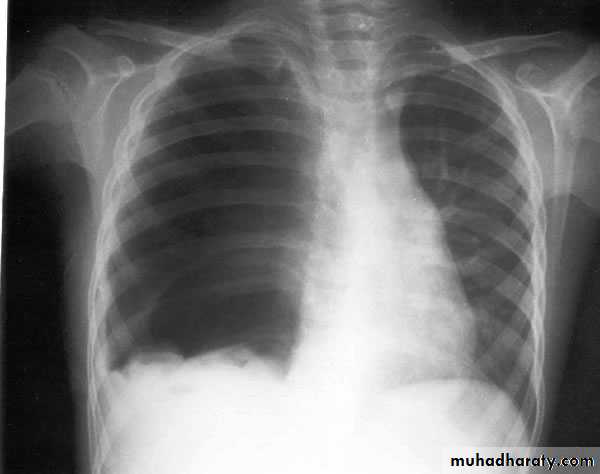

X-ray of pleural effusion

Massive right effusion